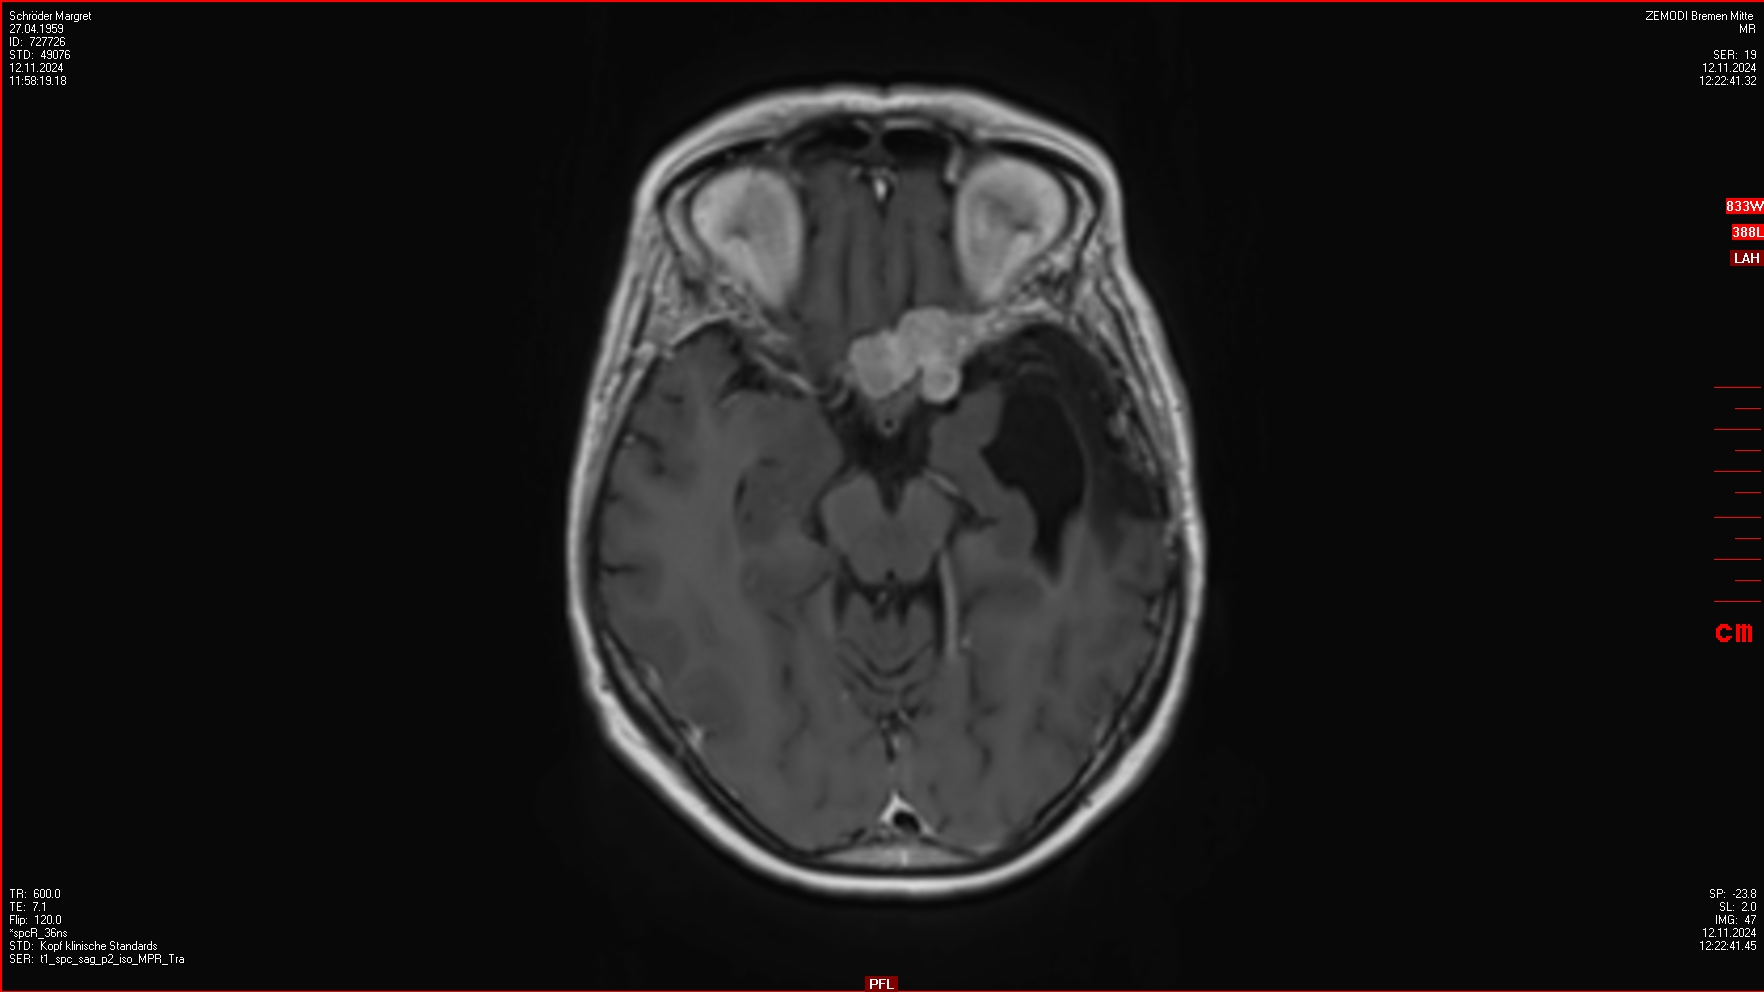

04.12.2024

OP im Krankenhaus Bremen-Mitte: 4 Menigeome (WHO III) entfernt, einige weitere verbleiben.

Ein ausführlicher Bericht von der OP findet sich hier.